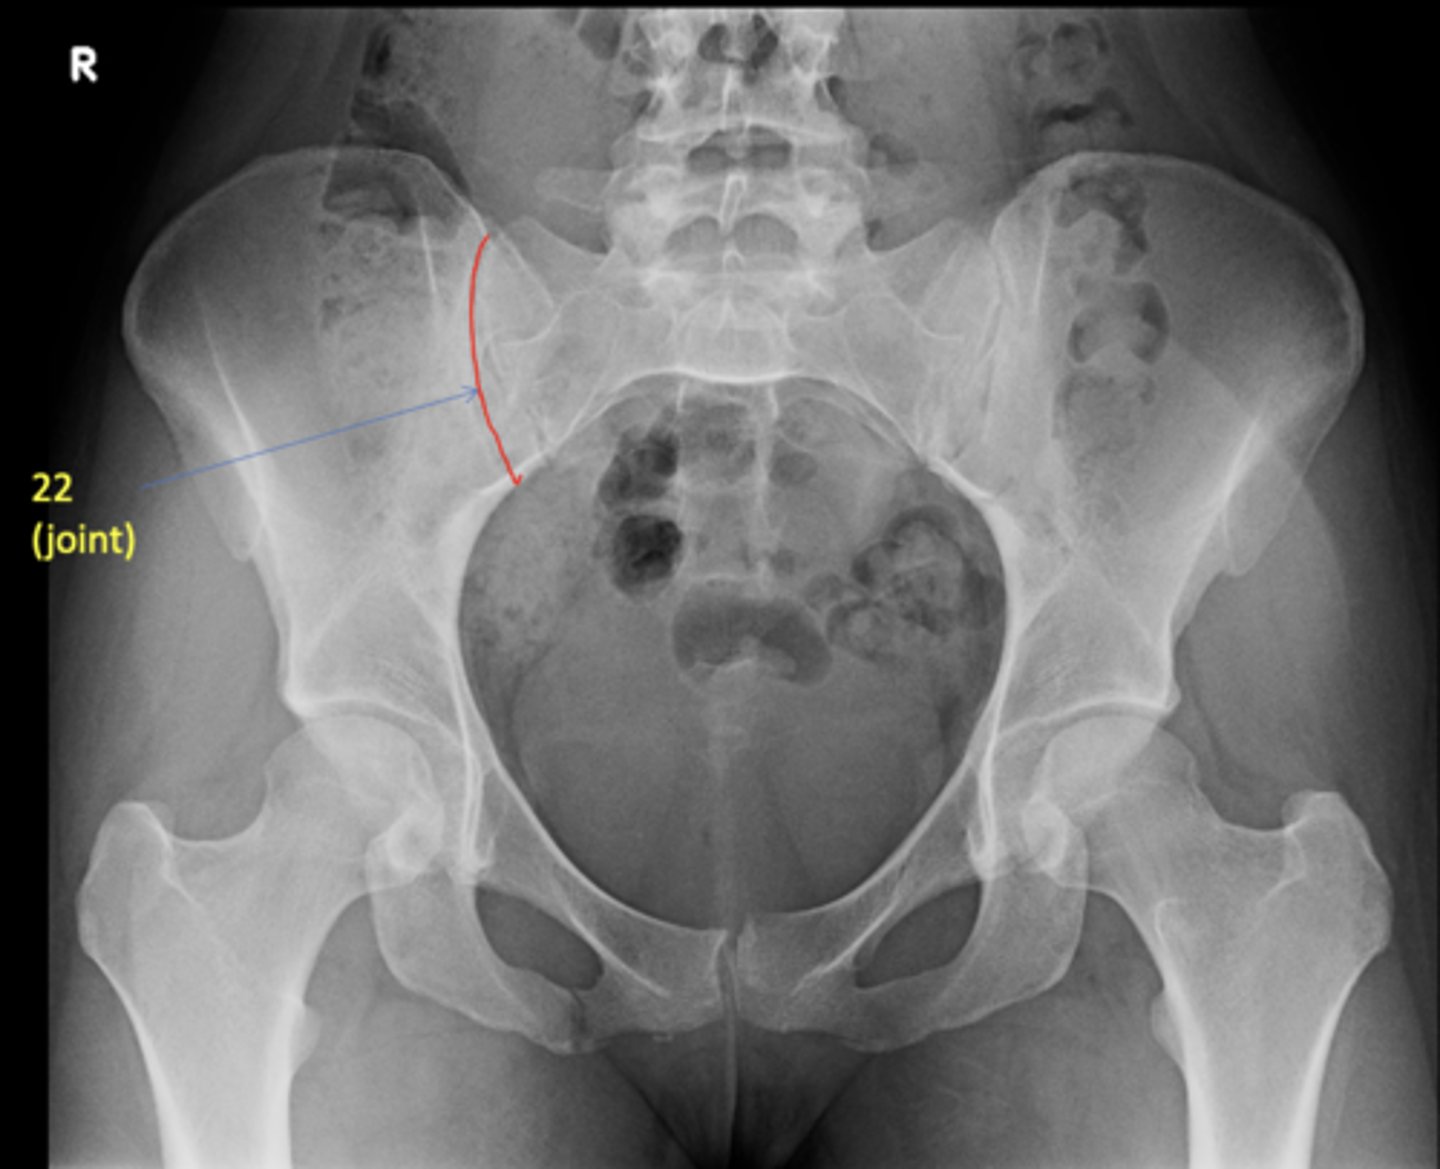

AP pelvis

20

New cards

Right anterior sacroiliac joint

ID 22 (joint)

<p>ID 22 (joint)</p>